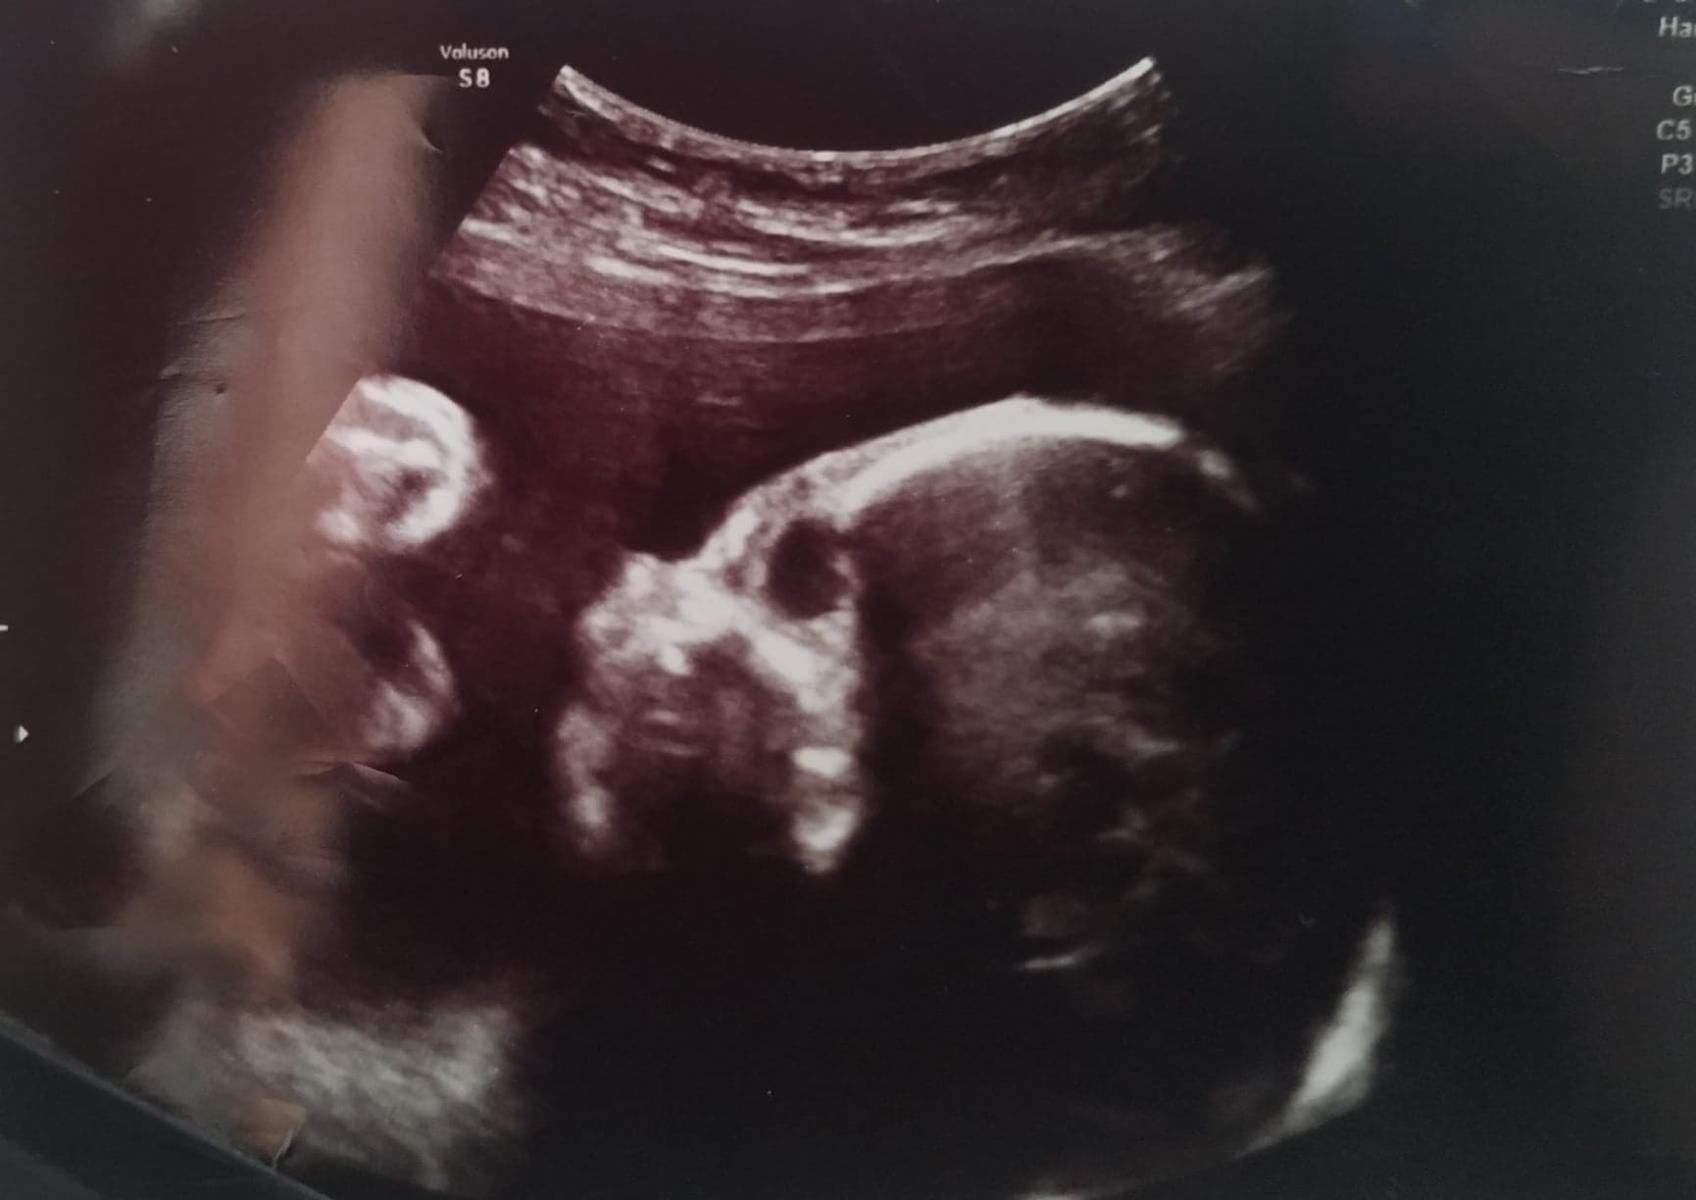

Płód z zespołem EdwardsaPłód z zespołem Edwardsa

Źródło zdjęć: © mat.pryw

W trakcie badania USG lekarz stwierdził u płodu szereg wad.

Dariusz Piontkowski o planach MEN dotyczących pomocy psychicznej dla dzieci

U płodu stwierdzono szereg wad

U płodu stwierdzono szereg wad © mat. prywatne